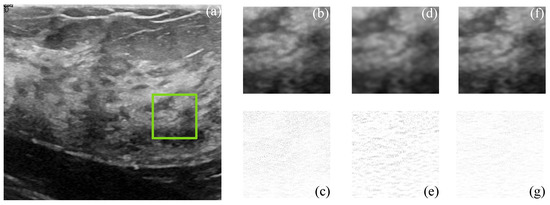

Despeckling of Ultrasound Images Using Block Matching and SVD in Sparse Representation

This work proposes a novel scheme for speckle suppression on medical images acquired by ultrasound sensors. The proposed method is based on the block matching procedure by using mutual information as a similarity measure in grouping patches in a clustered area, originating a new despeckling method that integrates the statistical properties of an image and its texture for creating 3D groups in the BM3D scheme. For this purpose, the segmentation of ultrasound images is carried out considering superpixels and a variation of the local binary patterns algorithm to improve the performance of the block matching procedure. The 3D groups are modeled in terms of grouped tensors and despekled with singular value decomposition. Moreover, a variant of the bilateral filter is used as a post-processing step to recover and enhance edges’ quality. Experimental results have demonstrated that the designed framework guarantees a good despeckling performance in ultrasound images according to the objective quality criteria commonly used in literature and via visual perception. Full article